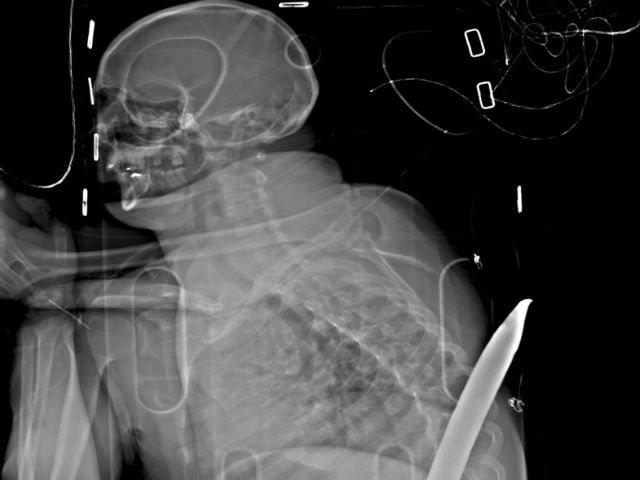

Hace tres años, un sudafricano sufrió un accidente minero que casi lo mata: una varilla industrial lo penetró de un lado al otro del cuerpo, entrando entre sus piernas y saliendo por su espalda, justo debajo de su omóplato. Ahora Daniel de Wet se clasificó para correr el próximo domingo en el ultramaratón Comrades.

De Wet perdió uno de sus riñones y sufrió otras lesiones internas por la palanca metálica de 1,8 metros (5,9 pies).

El terrible accidente ocurrió en enero de 2015, cuando cayó en la varilla en una mina en Carletonville, una zona minera de oro cerca de Johannesburgo. Con la palanca aún clavada, estuvo consciente mientras lo subieron a la superficie en una camilla. Los rescatistas lo transportaron en avión a un hospital, donde los cirujanos retiraron la palanca. De Wet fue dado de alta 19 días después.